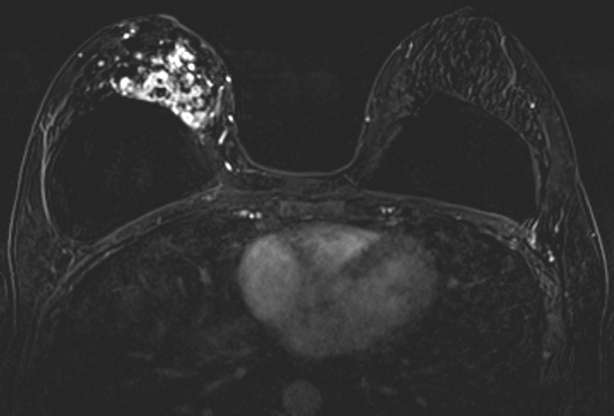

The combination of NME distribution and internal enhancement pattern with other morphologic MRI features and contrast kinetic curves (discussed separately) can help differentiate findings that are more or less suspicious for malignancy, but often NME findings ultimately require MRI-guided core needle biopsy for definitive diagnosis.4 Figures 1 through 3 demonstrate examples of biopsy-proven malignant NME.